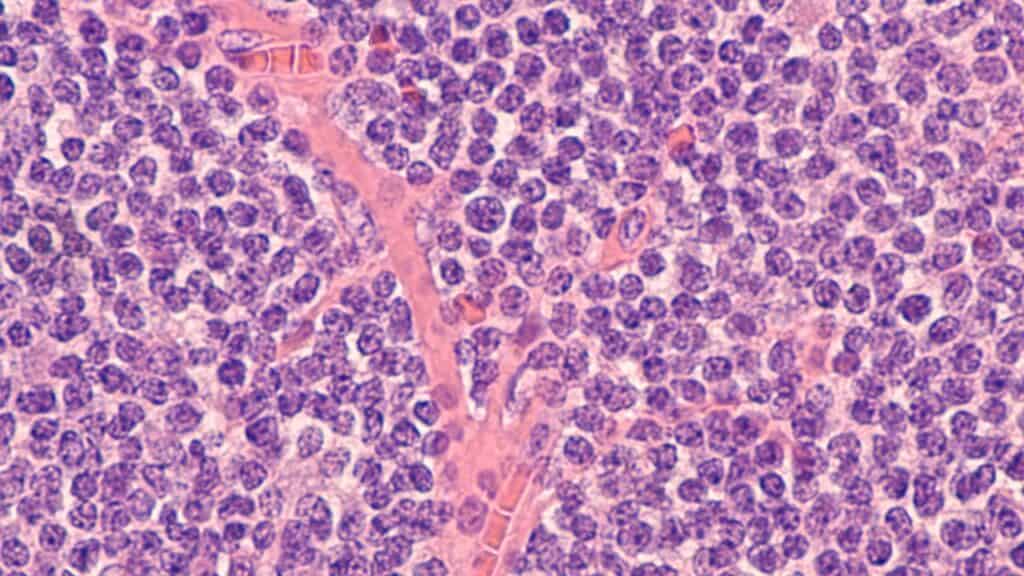

linfoma das células do manto